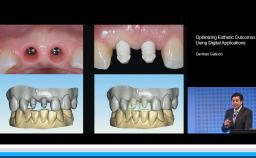

My ITI - German Gallucci

German Gallucci